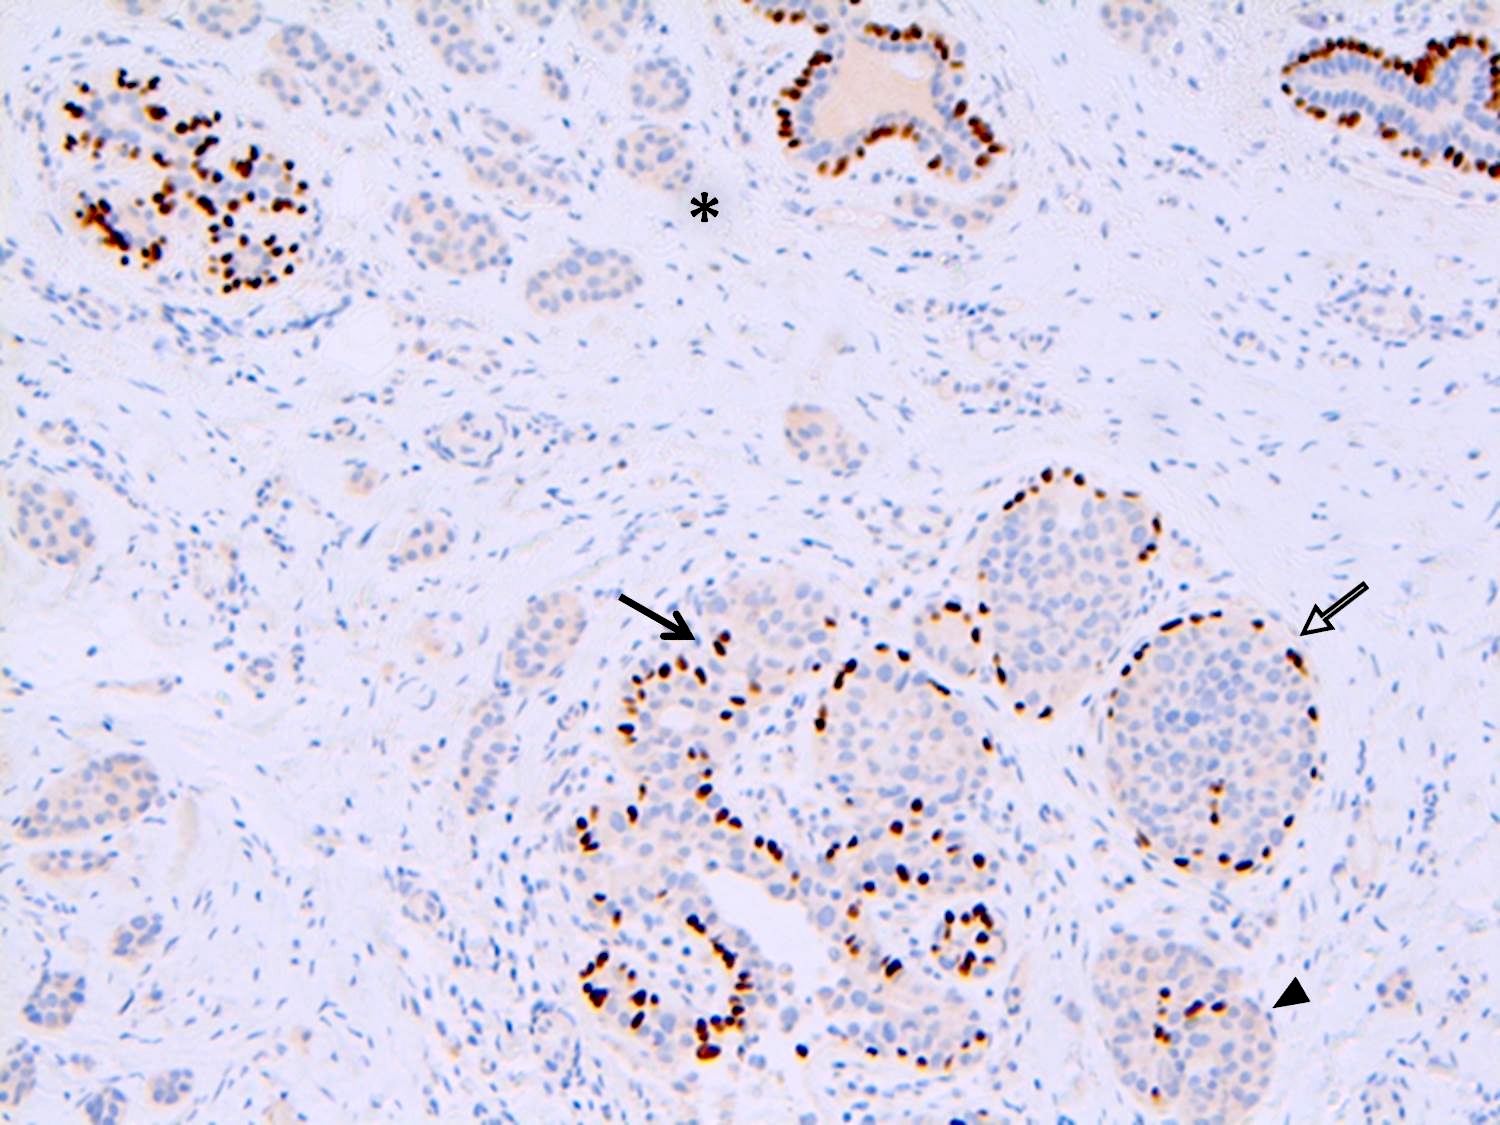

- Cases of LCIS or DCIS are distinguished based on histomorphology or by using E-cadherin and p120 catenin immunostains (Int J Clin Exp Pathol 2014;7:2551)

- Myoepithelial cells show weak positivity for E-cadherin due to the cross reactivity of P-cadherin

Positive stains

- Strong and diffuse nuclear ER and PR, low Ki67 proliferation index (Cancer 1996;78:1403)

Negative stains

- E-cadherin: most cases of classic LCIS demonstrate complete loss of E-cadherin staining

- In some cases of classic LCIS, attenuated or aberrant E-cadherin expression is observed, with scattered cells that show dot-like discontinuous / weak membranous staining or patchy cytoplasmic staining

- Atypical E-cadherin patterns or membranous positivity do not preclude the diagnosis of classic LCIS (Surg Pathol Clin 2018;11:123)

- Most cases show loss of expression of membrane beta catenin

- See Diagrams / tables

- Different combinations of alterations can result in different patterns of immunoreactivity

- Completely absent, weak and beaded, or aberrantly present in the cytoplasm in a dot-like pattern

- Rare cases (< 10%) may show membrane staining even though the protein is nonfunctional

Microscopic (histologic) images

Contributed by Anna Biernacka, M.D., Ph.D.